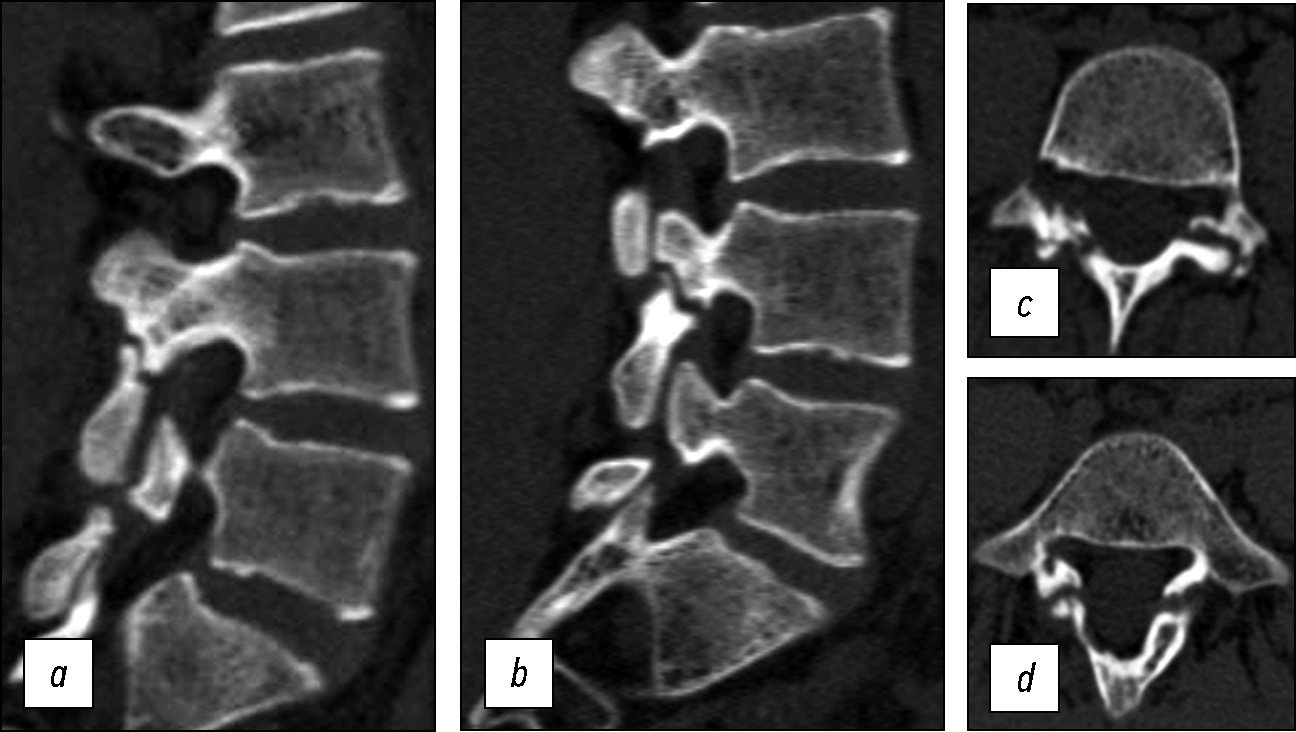

По данным мультиспиральной КТ пояснично-крестцового отдела позвоночника определяется билатеральный спондилолизный дефект межсуставной части дужки L4, L5 позвонка. Стадию спондилолиза, согласно классификации, предложенной К. Fujii и соавт. [13], можно отнести к завершённой на обоих уровнях (рис. 2). Также по данным рентгенографии и КТ отмечаются диспластические изменения задних элементов L5 позвонка в виде асимметрии дужки и изменённой формы остистого отростка. По данным МРТ пояснично-крестцового отдела позвоночника, признаки стеноза позвоночного канала отсутствуют, гидрофильность межпозвонковых дисков не нарушена (Pfirrmann — 1) (рис. 3).

Рис. 2. КТ поясничного отдела позвоночника: a — сагиттальный срез справа, b — сагиттальный срез слева, c — аксиальный срез на уровне дужки L4 позвонка, d — аксиальный срез на уровне дужки L5 позвонка.

Fig. 2. CT of the lumbar spine: a — sagittal slice on the right, b — sagittal slice on the left, c — axial slice at the level of the L4 vertebral arch, d — axial slice at the level of the L5 vertebral arch.